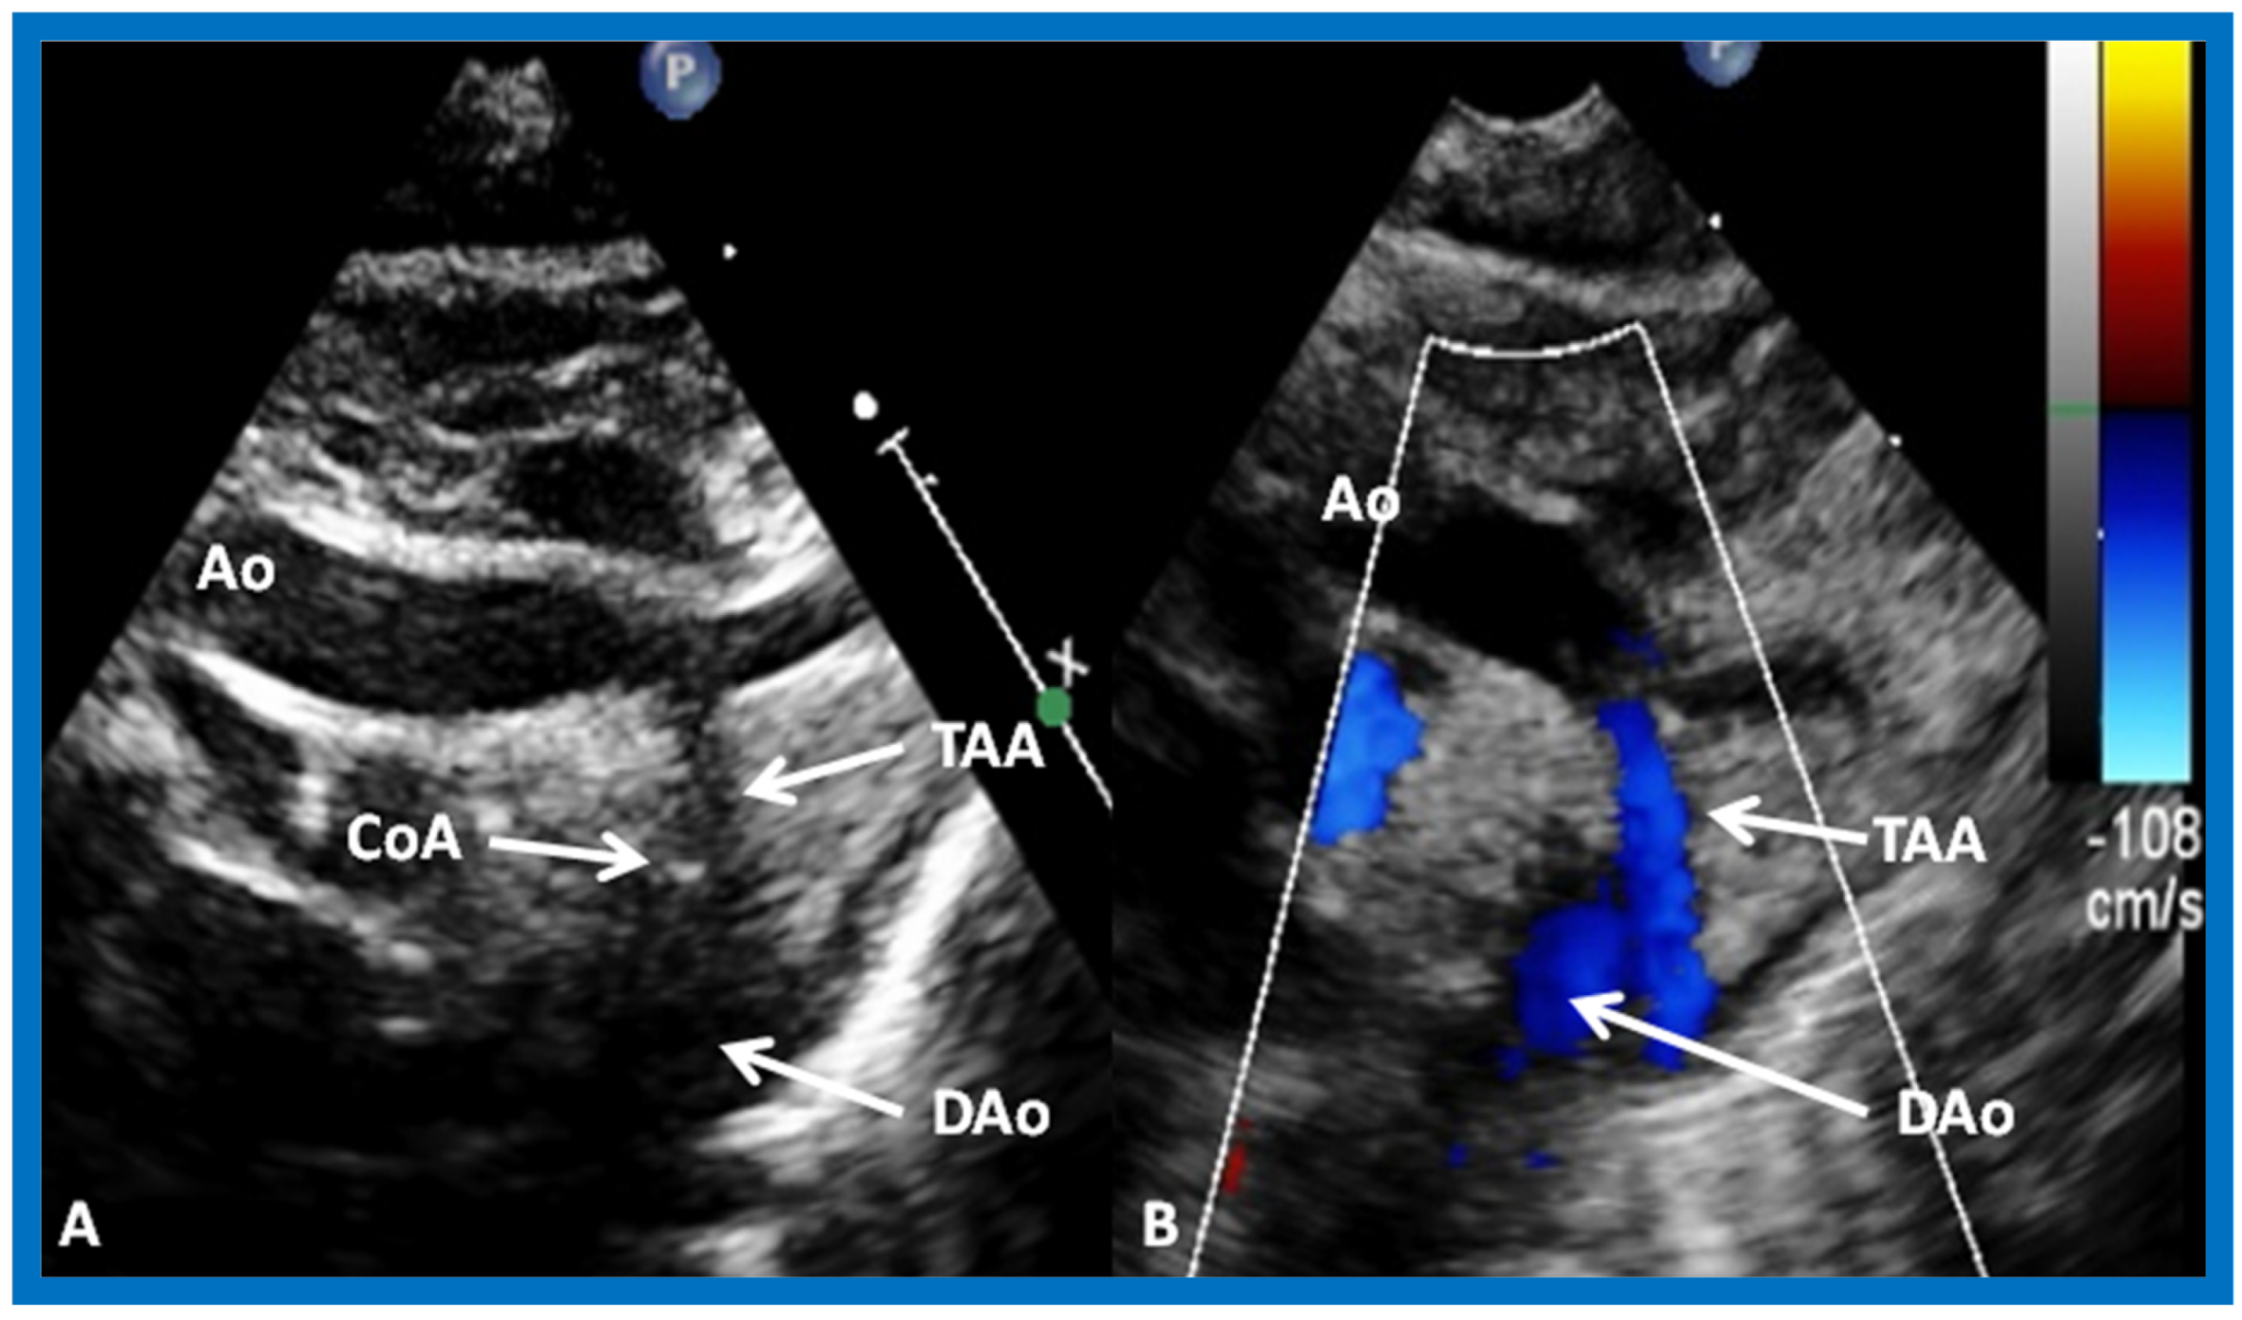

In Type II patients, the VSD may be small, causing obstruction to blood flow to the systemic circuit; therefore, the size of the VSD should be ascertained by 2D (Figure 21 and Figure 22), color Doppler (Figure 22), pulsed (Figure 25) and CW Doppler, as necessary. In these Type II patients, the high VSD velocity is indicative of subaortic obstruction. Interrogation of left ventricular outflow and PA region may reveal pulmonary or subpulmonary stenosis; the higher the velocity, the more severe the obstruction. Study from suprasternal notch may show aortic coarctation (Figure 26), which is not uncommon in patients with the Type II anatomy.

Figure 26.

Selected video frames from suprasternal notch views of the aortic (Ao) arch in 2D (A) and color flow (B) images of a neonate with tricuspid atresia and transposition of the great arteries demonstrating coarctation of the aorta (CoA) and hypoplastic transverse aortic arch (TAA). The association of CoA with tricuspid atresia plus transposition of the great arteries is well known. DAo, descending aorta. Reproduced from Rao P.S. [39].